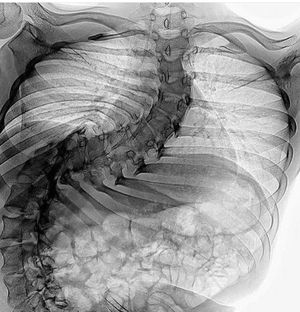

Incredibly severe scoliosis. They’ll have to do a spinal fusion. This patient likely has problems breathing due to the ribs affecting their lung capacity.

Scoliosis is a medical condition in which a person's spine has a sideways curve. The curve is usually "S"- or "C"-shaped. In some, the degree of curve is stable, while in others, it increases over time. Mild scoliosis does not typically cause problems, while severe cases can interfere with breathing